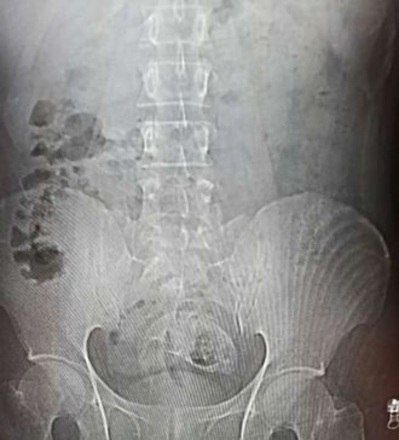

Ele então fez uma série de tomografias e raios X, que encontraram a fonte do problema

Se tratava de um peixe de água doce...

... alocado no reto do homem

Depois que o peixe, uma tilápia de Moçambique, foi encontrado, os médicos perceberam que era grande demais para ser removido por uma endoscopia de emergência

Eles então descobriram que as barbatanas espinhosas da criatura haviam causado rupturas no intestino grosso